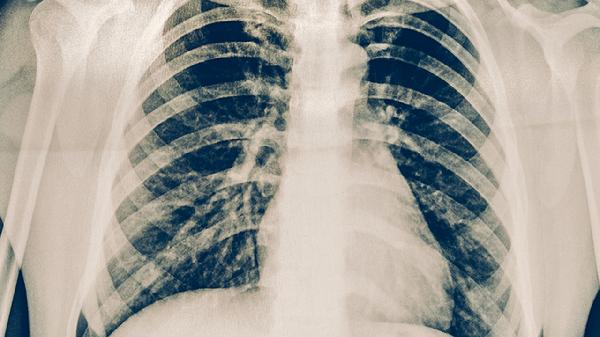

肺结核患者应严格遵医嘱完成6-8个月规范治疗,期间保持清淡饮食,每日摄入足量优质蛋白如鸡蛋、鱼肉帮助组织修复。适当补充维生素B族和维生素C有助于减轻药物副作用,可食用猕猴桃、燕麦等食物。保持规律作息与适度运动,但避免剧烈活动消耗体力。治疗期间若出现皮肤黄染、持续乏力等肝功能异常表现,需立即就医调整用药方案。康复后也需定期复查胸片,确保病灶完全吸收。